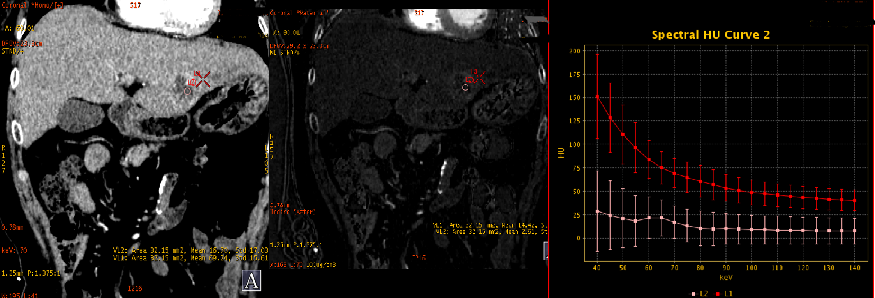

1、动脉期能谱曲线分析

肝左叶边缘环状强化部分及肝右叶小病灶具有基本一致的曲线(红/蓝);肝左叶病灶中心部分与肝右叶大病灶具有较接近的曲线(绿/粉)